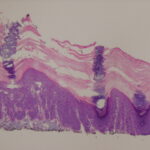

This variety of keratosis, sometimes referred to as florid keratosis, may easily be overdiagnosed as invasive squamous cell carcinoma by the unwary. Mild or moderate papillomatosis may be present. The epidermis is thickened in most areas and shows irregular downward proliferation that is limited to the uppermost dermis and does not represent frank invasion .A varying proportion of the keratinocytes in the stratum malpighii show a loss of polarity and thus a disorderly arrangement. Some of these cells show pleomorphism and atypicality (“anaplasia”) of their nuclei, which appear large, irregular, and hyperchromatic. Often the nuclei in the basal layer are closely crowded together. Some of the cells in the midportion of the epidermis show premature keratinization, resulting in dyskeratotic cells or apoptotic bodies characterized by homogeneous, eosinophilic cytoplasm with or without a nucleus. In contrast to the epidermal keratinocytes, the cells of the hair follicles and eccrine ducts that penetrate the epidermis within actinic keratoses retain their normal appearance and keratinize normally. Occasionally, cells of the normal adnexal epithelium extend over the atypical cells of the epidermis in an umbrella-like fashion. In some cases, abnormal keratinocytes extend downward on the outside of the follicular infundibulum to the level of the sebaceous duct and, less commonly, along the eccrine duct . |

In rare instances of actinic keratosis of the hypertrophic type, in addition to finding anaplastic nuclei in the lower epidermis, one finds areas of epidermolytic hyperkeratosis in the upper epidermis. These changes are like those seen in bullous congenital ichthyosiform erythroderma, in linear epidermal nevus, and as incidental epidermolytic hyperkeratosis in a variety of lesions. In areas of epidermolytic hyperkeratosis, one observes in the upper epidermis clear spaces around the nuclei and a thickened granular layer with large, irregularly shaped keratohyaline granules (39). Epidermolytic hyperkeratosis may occur also in lesions of solar cheilitis . |